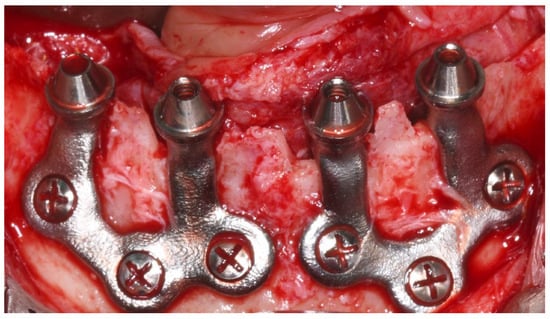

3.11.2. Surgical and Prosthetic Protocol

- Full-thickness flap elevation with identification of vital structures. (Prevents nerve injury and ensures proper implant bed access).

- Minimal osteoplasty when needed for passive fit. (Improves implant adaptation to the bony surface).

- Fixation with titanium screws at preplanned anchorage points. (Provides mechanical stability without intraosseous engagement).

- Strict aseptic handling of the implant. (Reduces risk of postoperative contamination).